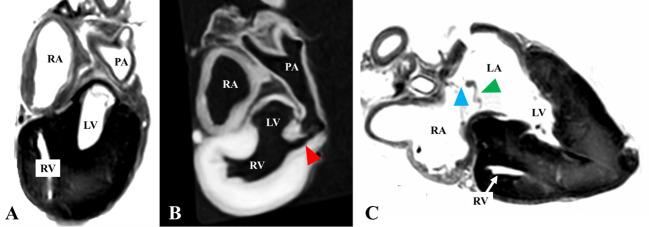

The necropsy of a 2-day-old Noma horse that died of weakness showed an enlarged cardiac base and a narrow cardiac apex, suggesting cardiac malformation. The excised heart underwent imaging to investigate its luminal structure. On three-dimensional magnetic resonance imaging, the right atrium and right ventricle were discontinuous. The right atrium communicated with the left atrium and the left ventricle communicated with the right ventricle. The lumen narrowed near the pulmonary artery valve. Since the same findings were observed on gross examination, the foal was diagnosed with tricuspid atresia with ventricular and atrial septal defects, along with subvalvular pulmonic stenosis.